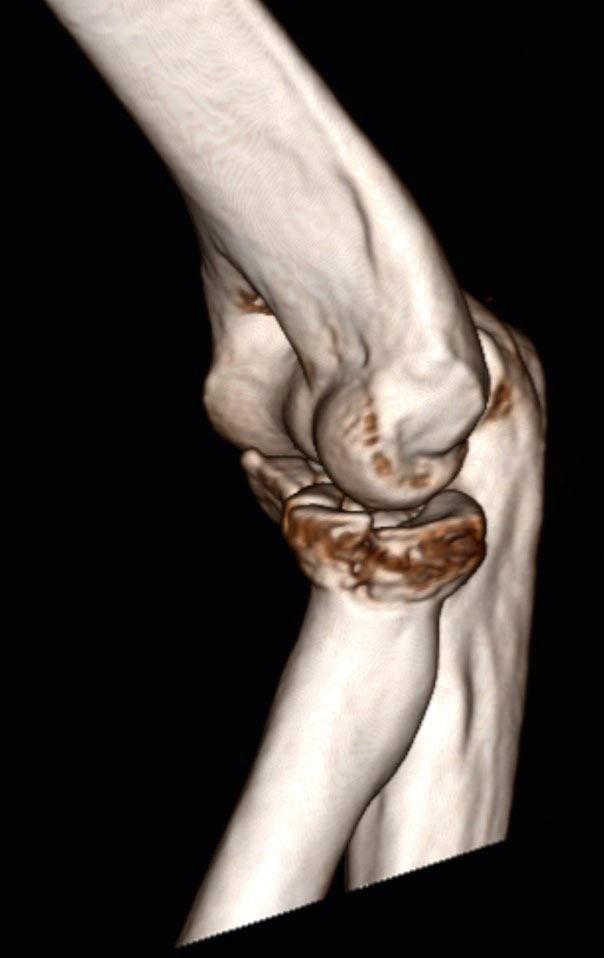

Ein 55-jähriger Bauarbeiter stürzte im Juli 2019 von einem Gerüst. Dabei zog er sich unter anderem eine multifragmentäre Radiusköpfchenfraktur und eine Spitzenfraktur des Processus coronoideus links zu (Abb. 6a). Eine operative Indikation war somit gegeben. Aufgrund der präoperativen Labordiagnostik wurde eine hyperglykämische Stoffwechsellage diagnostiziert, die prioritär behandelt werden musste. Während des konservativen Verlaufes entwickelte sich eine massive Bewegungseinschränkung und zunehmend Schmerzen beim Bewegen. Die initial geplante Operation wurde schlussendlich im Dezember durchgeführt. Es wurde eine Arthrolyse durchgeführt und das frakturierte Radiusköpfchen durch eine endoprothetische Versorgung ersetzt (Abb. 6b). Im ambulanten Setting erhielt der Patient wöchentlich dreimal Physiotherapie und 8 Wochen postoperativ eine statische Quengelschiene. Anfang März 2020 trat der Patient in die stationäre Rehabilitation durch den Autor ein. Die Schmerzsituation hatte sich deutlich verbessert, aber es hatte sich eine hartnäckige Bewegungseinschränkung vor allem in Ellbogenflexion manifestiert. Die aktive Beweglichkeit im Ellbogen links belief sich bei Eintritt bezüglich Flexion/Extension auf 80/10/0, bezüglich Pronation/Supination auf 80/0/80 (aus 70° Ellbogenflexion), passiv in Flexion/Extension auf 85/10/0, bezüglich Pronation/Supination auf 85/0/85. Das Endgefühl in Ellbogenflexion war fest-elastisch (eher kapsulär), und der Patient berichtete über gelegentliche Parästhesien in der linken Hand. Die statische Quengelschiene versuchte er in der Nacht in endgradiger Flexion zu tragen. Der Patient stellte sie jeweils so stark ein, dass er sie nur jeweils 1 Stunde lang tragen konnte und sie dann schmerzbedingt wieder abziehen musste. Die vermehrten Schmerzen zogen sich jeweils bis zum nächsten Morgen hin. Im stationären Rehabilitationsaufenthalt wurde mit 3 bis 4 Physiotherapiesitzungen pro Woche und täglich begleitenden medizinischen Trainingstherapien gestartet. Die statische wurde durch eine dynamische Quengelschiene ersetzte und die Dosierung „Quengelung in der Remodulierungsphase“ angewendet. Somit konnte der Patient die Schiene nachts 3 bis 4 Stunden lang tragen, bis es für ihn unangenehm wurde. Die morgendlichen zusätzlichen Schmerzen blieben ab dem zweiten Tag aus. Nach 3 Wochen belief sich die aktive Flexion auf 90°, die passive auf 95°. Zusätzlich wurde versucht, den nach der manuellen Mobilisation auftretenden „Jojo-Effekt“ bis zur nächsten Therapiesitzung mit einer einstündigen Quengeltherapie mit derselben Dosierung zu minimieren. Nach weiteren 2 Wochen konnten bei der Austrittsuntersuchung folgende Werte erhoben werden: aktiv bei Flexion/Extension 95/10/0 bzw. bei Pronation/Supination 85/0/80 (aus 90° Ellbogenflexion), passiv bei Flexion/ Extension 100/5/0 bzw. bei Pronation/ Supination 85/0/85 (Abb. 6c). Dies ist ein erfreulicher Fortschritt und zeigt aus der klinischen Erfahrung des Autors heraus, dass eine wundheilungsphasenadaptierte Dosierung im Einsatz mit Quengelschienen eine effektvolle Unterstützung der Manuellen Therapie darstellt. Dieses stationäre Setting wurde nun in die ambulante Nachbehandlung übertragen.